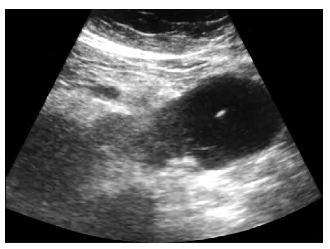

Ecografía (USG): accesibilidad y rapidez

La ecografía es la técnica más utilizada por su disponibilidad, bajo costo y capacidad de visualización en tiempo real. Además, no implica exposición a radiación, lo que la convierte en una opción segura y eficiente.